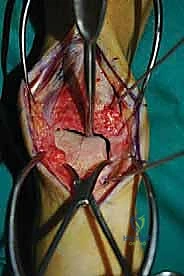

الغوص العميق في جراحة الطعم الخيفي الهيكلي (Structural Allograft Reconstruction)

يهدف هذا الإجراء العبقري إلى استبدال الغضروف والعظم التالفين والميتين بنسيج سليم تماماً مأخوذ من متبرع متوفى (طعم خيفي - Allograft). هذا الطعم يتم تعقيمه وحفظه في بنوك الأنسجة العالمية وفقاً لأعلى المعايير الطبية الصارمة لضمان خلوه من أي أمراض معدية والحفاظ على حيوية الخلايا الغضروفية.

- الترميم التشريحي الحقيقي: يسمح باستعادة الشكل الهندسي الدقيق لعظم الكاحل، بما في ذلك المنحنيات المعقدة لكتف التالوس.

- توفير غضروف طبيعي (Hyaline Cartilage): الغضروف المزروع هو غضروف زجاجي طبيعي،